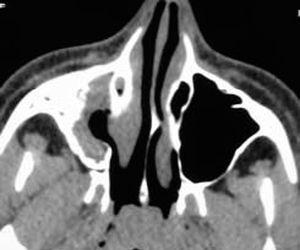

La exploración clínica fue normal. No se observó tumefacción ni palidez de la mucosa nasal. Tampoco se apreciaban asimetrías faciales. La exploración endoscópica nasal revelaba un discreto desplazamiento lateral de la apófisis unciforme. Los resultados de prick-test fueron negativos. La radiografía de tórax no mostraba alteraciones patológicas. En la radiografía de senos paranasales se apreciaba una ocupación completa del seno maxilar derecho, por lo que fue diagnosticada de sinusitis maxilar, y se le pautó tratamiento antibiótico. En la radiografía realizada 2 semanas más tarde se mantenía la imagen de ocupación, por lo que se decidió realizar una TC, en la que se apreciaba una opacificación parcial del seno maxilar derecho, con desplazamiento lateral de la pared infundibular medial, con incipiente descenso de la pared orbitaria inferior y retracción de la mucosa del meato medio, sin niveles hidroaéreos endosinusales (figs. 1 y 2). Dada la ausencia de signos, síntomas y complicaciones, la actitud terapéutica ha sido expectante. Si se produjera una evolución hacia el enoftalmos, se propondría tratamiento quirúrgico dirigido a la liberación del ostium del seno maxilar.

Figura 2.TC de senos paranasales (proyección axial). En esta imagen se aprecia la retracción de la mucosa sinusal, el menor tamaño del seno maxilar derecho, así como la incipiente retracción ósea.

Los criterios diagnósticos radiológicos de ACM incluyen opacificación del seno maxilar, desviación lateral de la pared infundibular medial y retracción de la mucosa sinusal 3-5,9-11. Estos criterios están presentes en el caso que aportamos (figs. 1 y 2).